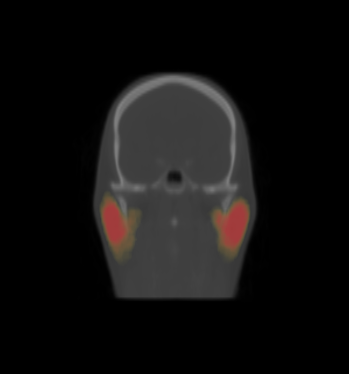

- We have 20 datasets for H&N including lungs and chests. For example

- We selected the ROI of every data excluding lung and chest. For each data there exist the segmentations of brain stem, left and right parotids. For example

- We constructed the average atlas of 20 datasets of ROI, and merged the segmentations into the average atlas. These segmentations are the probability maps of

brain stem, left and right parotids.